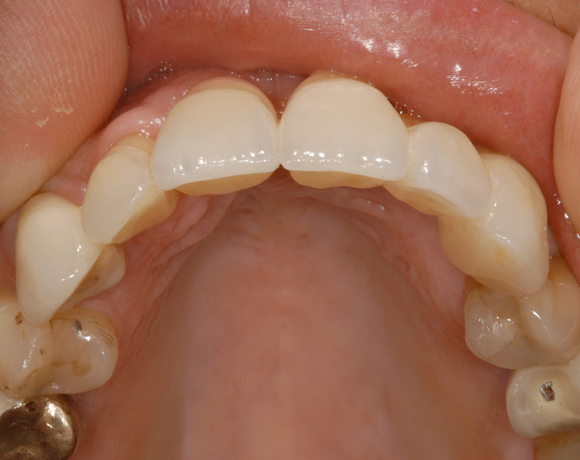

Das vollkeramische zweiteilige Implantat hat durch seine weiße Farbe im Frontzahnbereich keine ästhetischen Nachteile.

Im vorliegenden Patientenfall mussten die 11 bis 22 aus parodontalen Gründen extrahiert werden. Die Zähne hatten Lockerungsgrad III, und es bestand ein starker horizontaler Knochenabbau. Das Ergebnis zeigt die Abschlusssituation nach Knochenaufbau und der Insertion von drei Vollkeramikimplantaten.